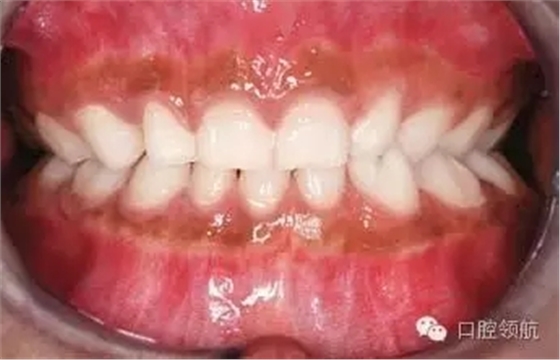

圖2.12中該名15歲男性患者的牙列特征有哪些?

圖2.12

● 上頜中切牙和側(cè)切牙為融合牙。

● LL5缺失。

● UL5,UR5和LR5阻生。

● LLE,ULE和LRE滯留。

● 尖牙和前磨牙的牙根發(fā)育滯后。